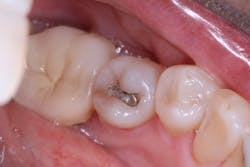

Most posterior teeth are a Vita shade A1/B1, an easy color to blend using many composites. The real test of a universal-shaded composite is its behavior in a darkly shaded posterior tooth. A lower bicuspid (tooth No. 20) with Vita shade C2 required removal of a defective amalgam restoration (figure 3). The site was not anesthetized; it was isolated using a DryShield, and the amalgam removed as a chunk using the Fissurotomy bur (figure 4).